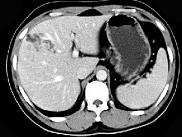

问题 男,33岁,右上腹不适,CT所见如图,最可能诊断是()

选项 A.肝内胆管囊肿 B.淋巴管瘤 C.胆管细胞癌 D.肝脓肿 E.肝囊肿

答案 B